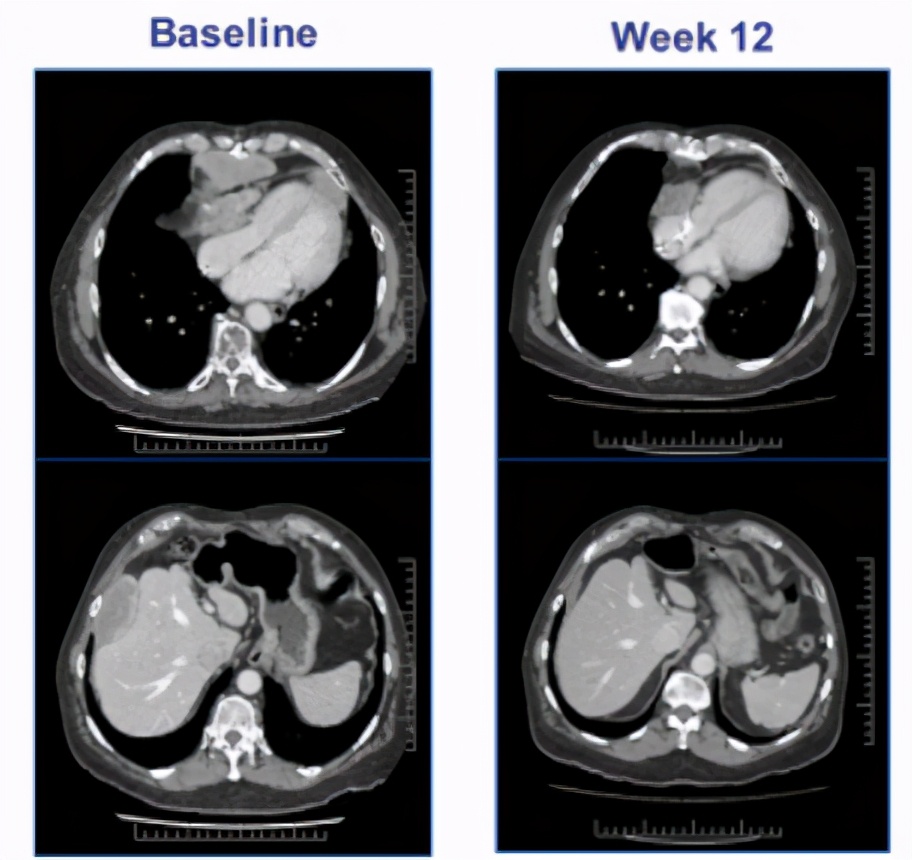

会议上报道了一位67岁的男性晚期滑膜肉瘤患者,MAGE-A4高表达(100% 3),接受9.95*10^9ADP-A2M4 T细胞治疗12周后,最大的肿瘤病灶(155mm)缩小了45%,随着进一步的治疗,肿瘤缩小了71%。